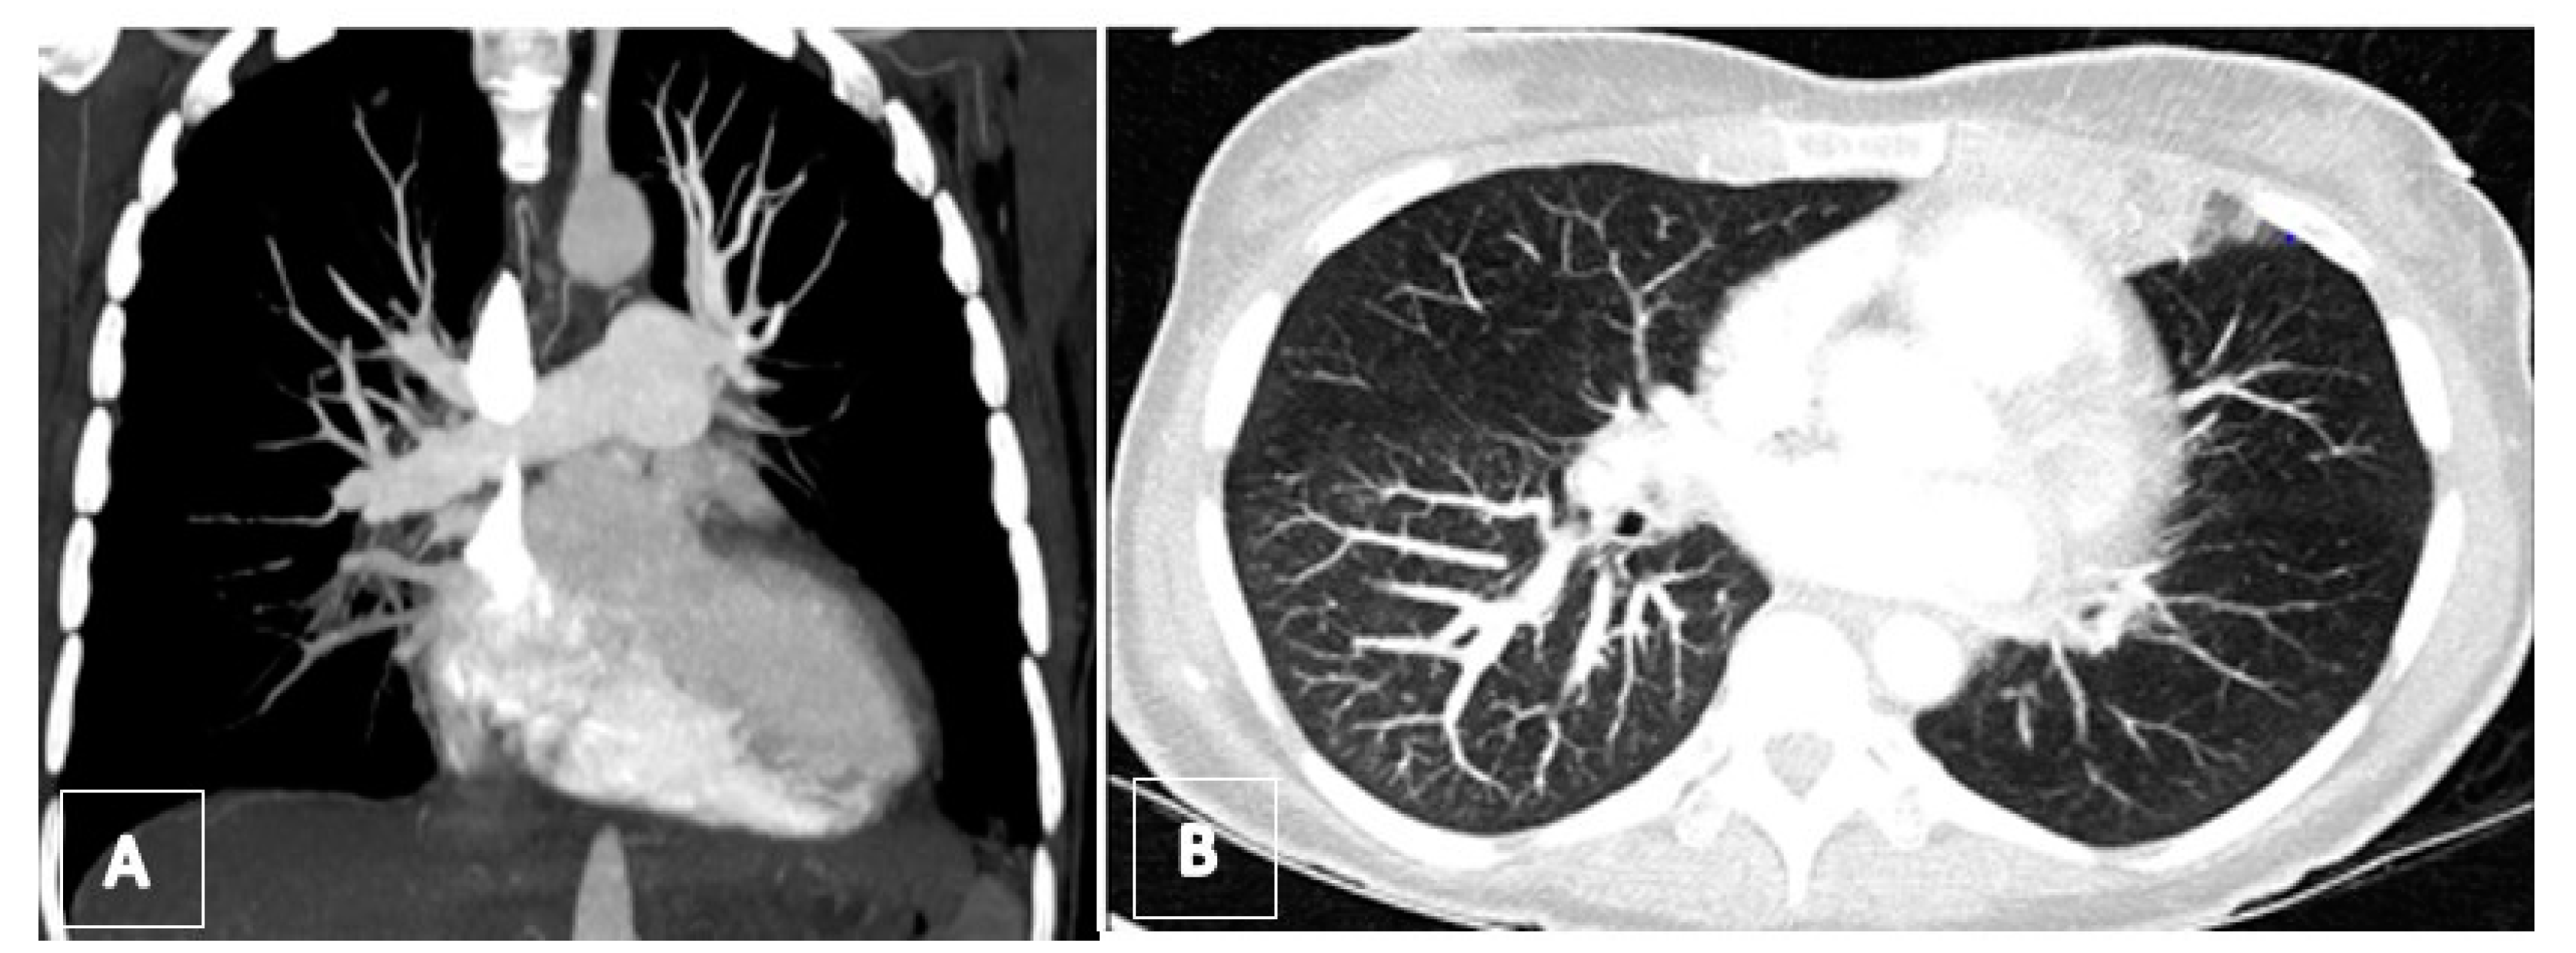

3.3. Imaging

3.4. Computed Tomography Pulmonary Angiography (CTPA)